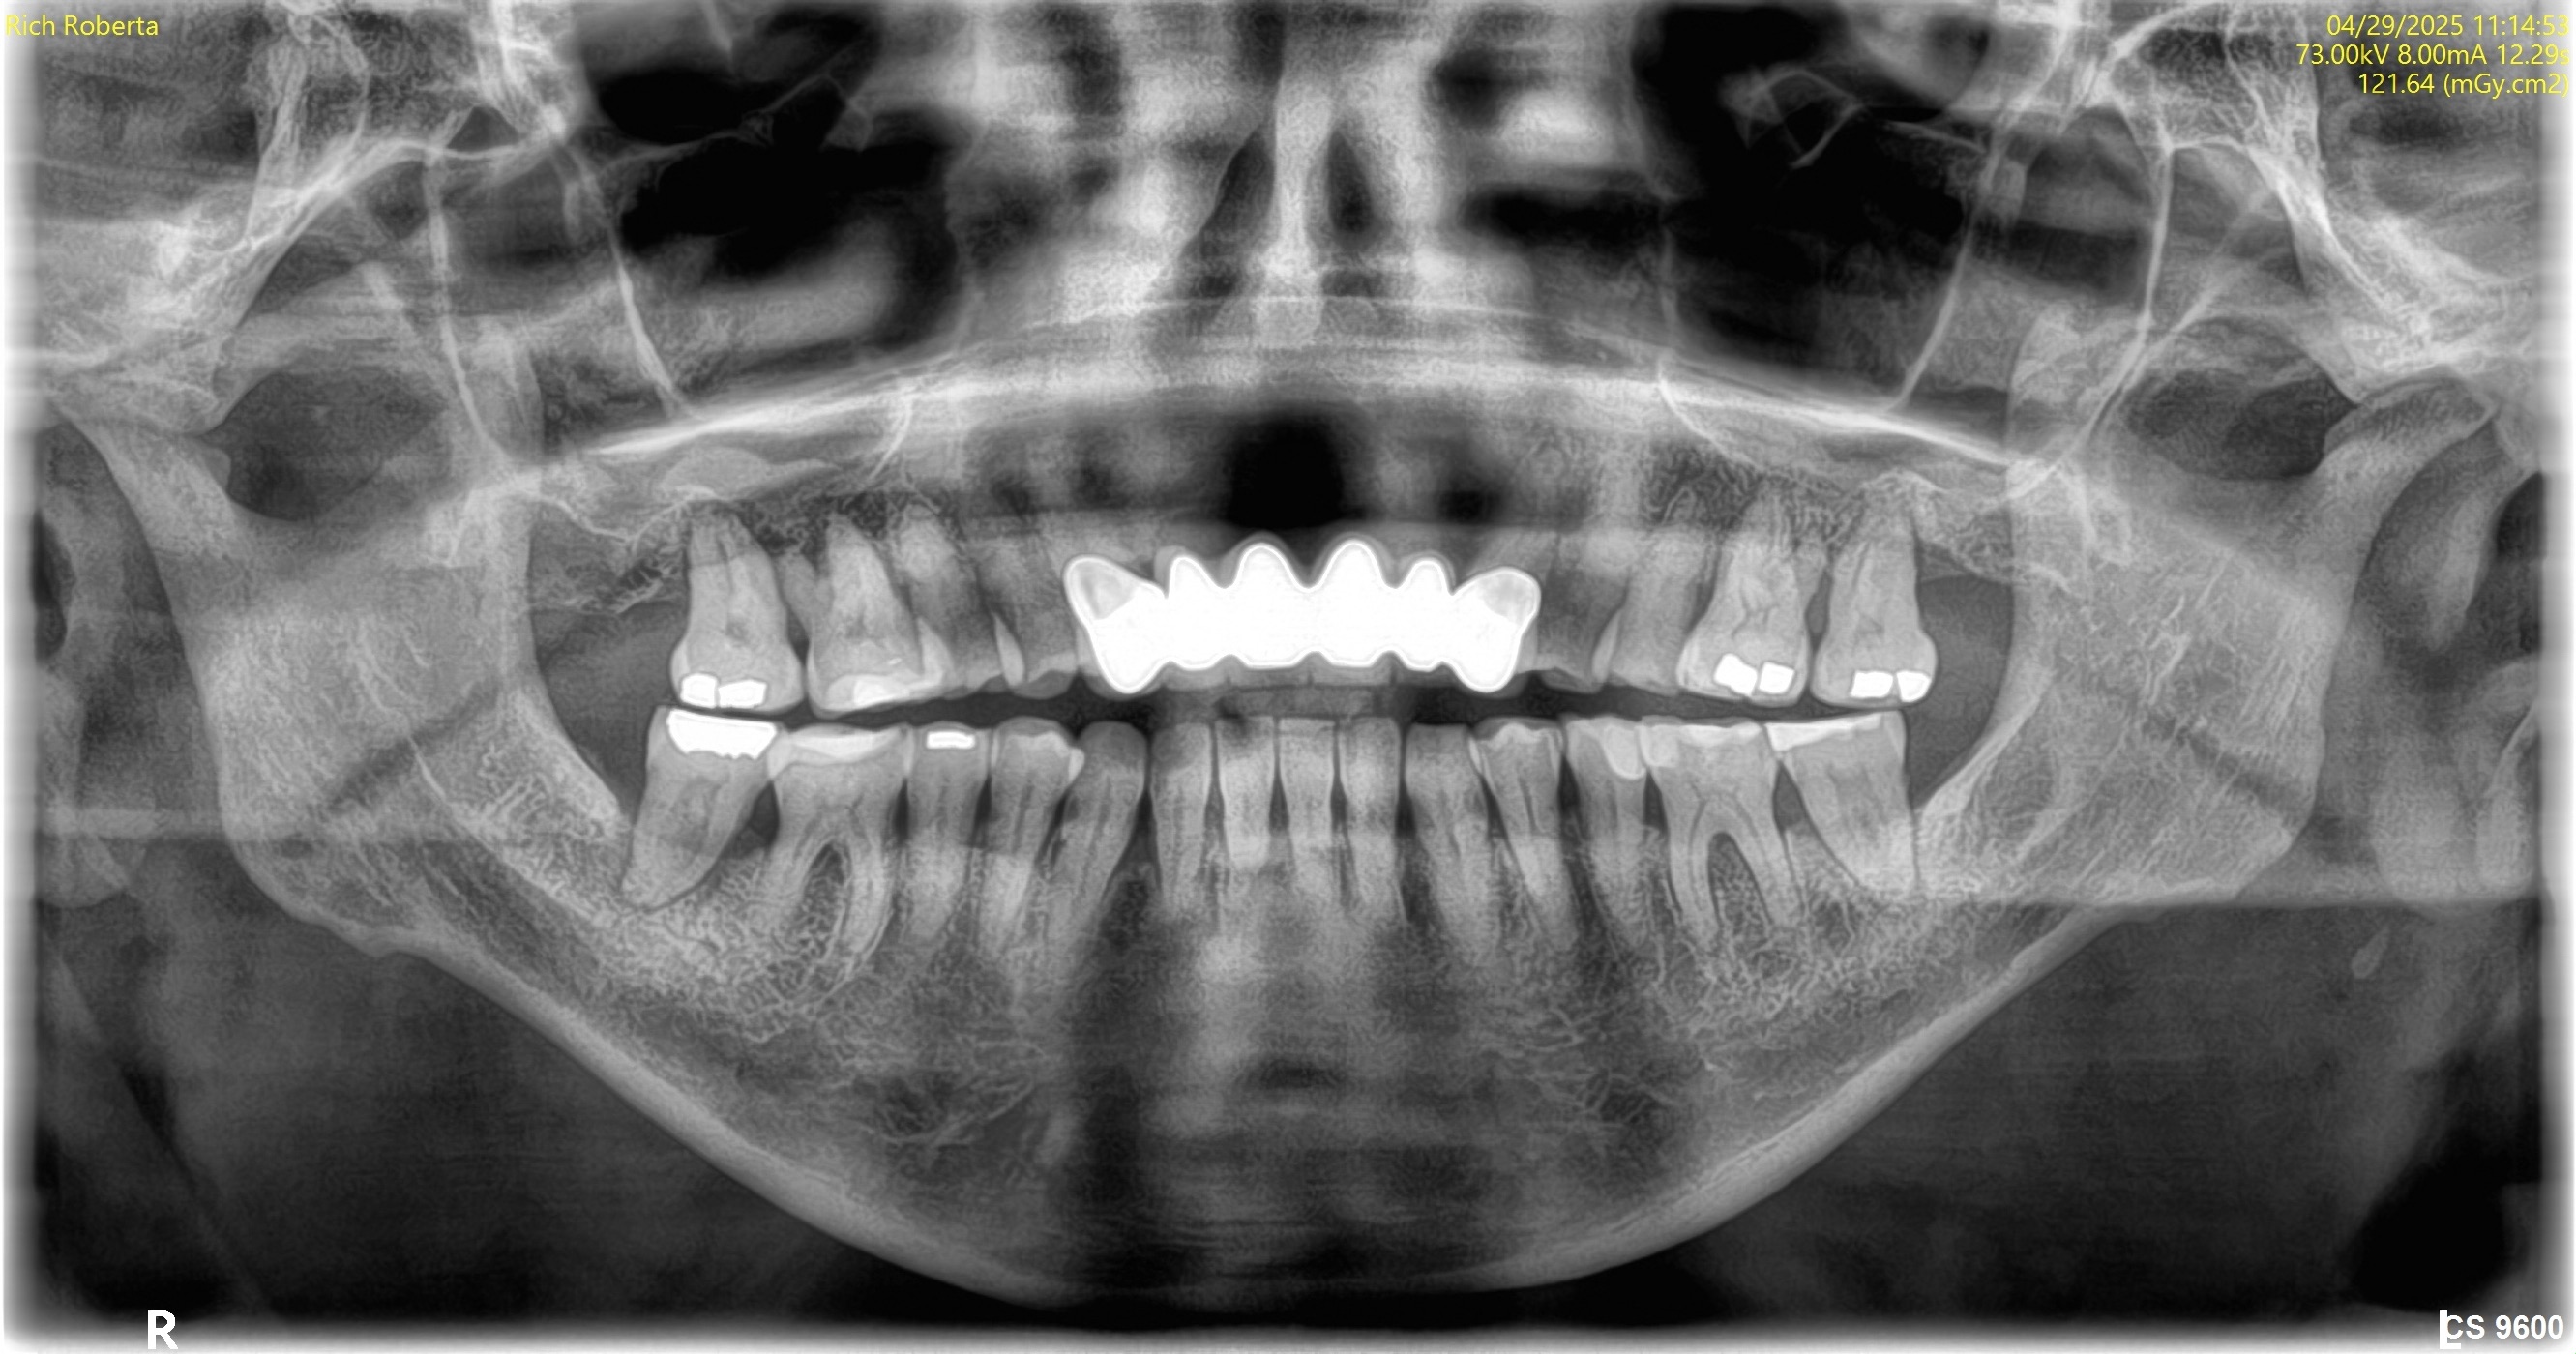

April 29, 2025Comprehensive exam, CBCT full visualization, and baseline questionnaire.

Visual Case Progression

All clinical images are shown at a consistent size for easy comparison.

Before & After (Pano Images)